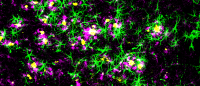

Cleaning the brain. A green tracer fluid flows through the brain's glymphatic system, a recently discovered waste disposal system. The system moves waste along the outer edges of the brain's blood vessels (red). Images provided by Kai Chen.